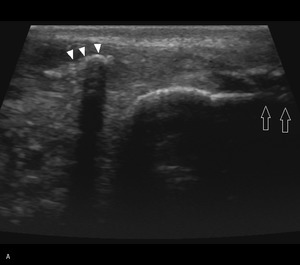

Pacjent, lat 52, zgłosił się do lekarza ortopedy z powodu silnego bólu w okolicy prawej pięty, który wystąpił nagle poprzedniego dnia podczas treningu piłki nożnej. Pacjent uprawia sport regularnie. Do tej pory nie cierpiał z powodu żadnych dolegliwości bólowych tej okolicy, a początek bólu nie był związany z bezpośrednim urazem. Podczas badania stopy okolica ścięgna Achillesa (piętowego) była obrzęknięta i bolesna, ruchy czynne w stawie skokowym znacznie ograniczone. Stwierdzono brak palpacyjnej bolesności w okolicy kostki przyśrodkowej i bocznej z zachowaną stabilnością w ruchach na boki.

Obrzęknięta okolica ścięgna Achillesa wraz z nagłym początkiem dolegliwości wskazuje na jego zerwanie. Niemniej możliwość wykonywania czynnych ruchów w stawie skokowym, nawet w niewielkim zakresie, przemawia za innym rozpoznaniem. Nie występuje też wyczuwalna luka w ścięgnie, jednak może być ona maskowana obrzękiem tej okolicy. Zapalenie kaletki głębokiej ścięgna Achillesa również może wywołać podobne objawy. Często wiąże się ono z występowaniem wyrośli kostnej na kości piętowej (deformacja Haglunda), która drażniąc kaletkę, wywołuje jej stan zapalny. Do złamań zmęczeniowych kości piętowej najczęściej dochodzi u żołnierzy oraz sportowców, którzy biegają długie dystanse po twardym podłożu. Jednakże w tym wypadku jest to mało prawdopodobne rozpoznanie, ponieważ pacjent może stanąć na pięcie oraz nie ma krwiaka i obrzęku tej okolicy.